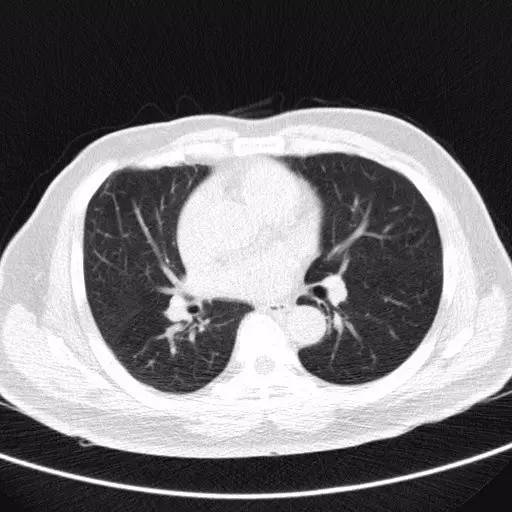

胸部CT

CT比胸片具有更高的灵敏度和特异度,能够显示小结节的二维形态,还能清晰显示小结节周围组织的影像学特点。胸部CT扫描不仅能够更清晰的观察肺部小结节的形态及大小,还能通过不同时间的CT图像动态的比较小结节的变化情况。胸部薄层CT具有更高的分辨率,应该作为评估肺部孤立性小结节性质的首选影像学检查方法。

低剂量螺旋CT

欧美和日本自90年代后以低剂量螺旋CT(LDCT)为主要检查方法的大型普查项目均显示肺癌筛查恶性检出率在1%~2%,早期肺癌检出率80%以上,5年甚至10年生存率达80%以上,预期10年生存率可达88%。所有研究数据均表明通过筛查可以改善肺癌病人的生存。目前LDCT技术上日趋成熟,扫描辐射剂量约为2.0mSV,明显低于常规CT,是最有效的肺癌筛查手段。

而美国美国国立癌症研究院(NCI)的一项长达10年的肺癌筛查试验的最新结果表明,对高危人群包括吸烟者或前吸烟者的螺旋CT筛查可以使肺癌死亡率降低约20%,这一结论第一时间于2010年10月通过NCI官网发布,并于2011年在新英格兰杂志上报道。

这项由NCI发起的研究耗资25亿美元,始于2002年,全美33个研究点共有53000个年龄在55-74岁的吸烟者参加,他们被随机分配到低剂量螺旋CT(LDCT)组和X线胸片(XR)组,筛查一年一次共3次,随后再追踪观察5年,结果LDCT组肺癌死亡354人, X线组肺癌死亡442人,死亡率LDCT组较X线组降低约20.3%